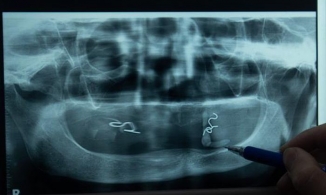

Ngày 15/12, một nữ nhân viên y tế ở bang Alaska (Mỹ) đã gặp phải phản ứng dị ứng nghiêm trọng sau khi tiêm vaccine Covid-19 của hãng Pfizer, người này bắt đầu xuất hiện triệu chứng chỉ 10 phút sau khi tiêm.

Theo tờ The New York Times, nhân viên y tế này đã chủng ngừa tại Bệnh viện khu vực Bartlett ở Juneau, Alaska, Mỹ. Ngay sau đó, bà đã phải nhập viện và hiện vẫn đang được theo dõi chặt chẽ tại bệnh viện. Cá nhân bà không có tiền sử dị ứng với thuốc hay vaccine.

Tiến sĩ Lindy Jones, Giám đốc y tế khoa cấp cứu của bệnh viện cho biết, nữ nhân viên y tế trung tuổi bị phát ban khắp mặt và cơ thể, khó thở, nhịp tim tăng cao. Khi xử trí sốc phản vệ, ban đầu bà được tiêm epinephrine để điều trị dị ứng theo phương pháp tiêu chuẩn. Các triệu chứng đã thuyên giảm nhưng sau đó lại tái phát và bác sĩ chỉ định cho bà tiếp tục dùng steroid và truyền epinephrine.

Khi ngừng truyền thuốc bà lại di ứng trở lại và được chuyển đến phòng hồi sức cấp cứu tích cực theo dõi suốt đêm. Đến sáng 16/12 đã ngưng dùng thuốc và đến hiện tại, sức khỏe đã trở lại bình thường. Nữ nhân viên y tế này bày tỏ mình vẫn tin tưởng vào vaccine.